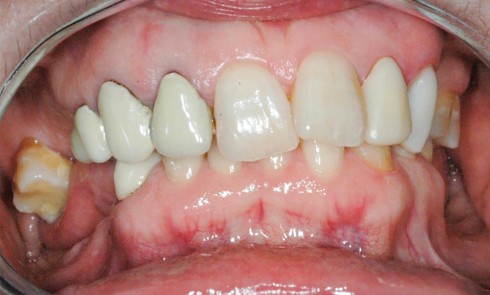

Article réservé à nos abonnés Reconstruction en antéposition

Les chirurgiens-dentistes sont parfois confrontés à des réhabilitations orales complexes. Les difficultés peuvent être dues à des délabrements ou des...